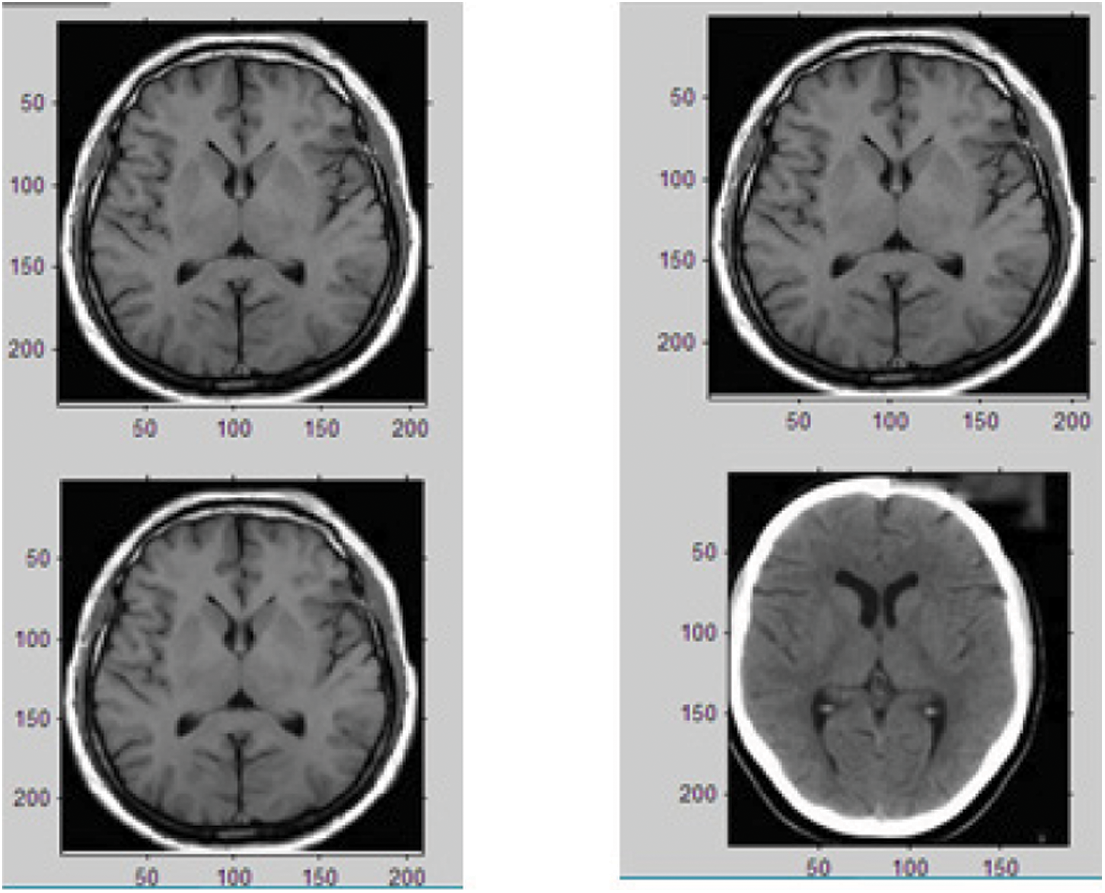

On extracting the four levels of NSCT coefficients from the input multimodal source image, the NSCT fusion rule is applied to amalgamate the inferior frequency component and the majority frequency components and the particle blended output figure is acquired. The second phase of process, Joint Sparse Representation (JSR) is applied on the NSCT coefficients and the initial process of preprocessing is performed before executing the process of extracting the sparse coefficients from the input multimodal source images. The multi-level of extracted sparse coefficients of the input source image is depicted in Fig. 12.

Figure 12: Sparse coefficients extraction from the input image

The coefficients extracted from the process of Non Sub sampled Contourlet Transform and the Joint Sparse Representation is fused together to acquire the concluding level of blended figure as depicted in Image 13. The Fig. 13 portrays the fusion process of the proposed hybrid NSCT process and Joint Sparse Representation process and the final fusion image provides depth information on the input multimodal image.

Figure 13: Final fused image by the proposed NSCT-JSR process